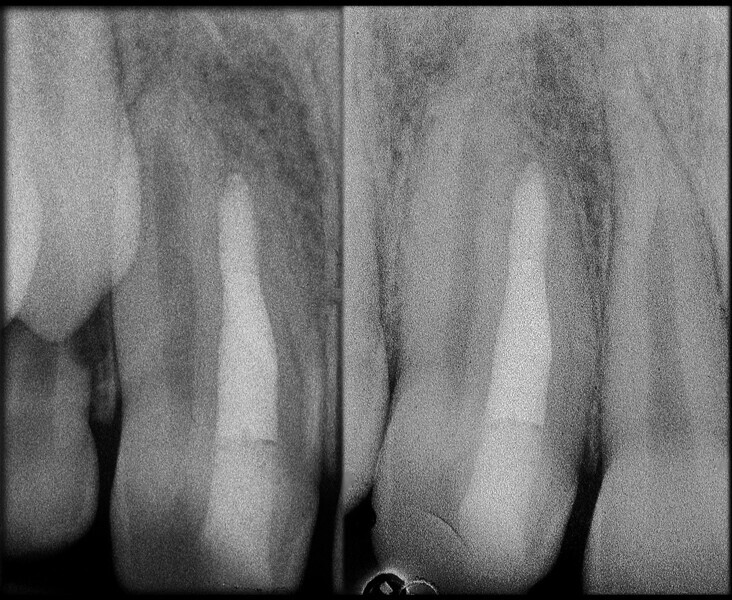

Use of 3D technology in the diagnosis and treatment of endodontic disease